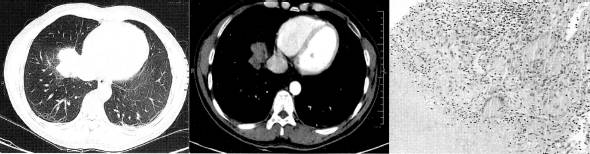

五、肺真菌病

如肺隐球菌病、组织胞浆菌病、球孢子菌病等(图10、图11),部分可表现为不规则肺部球形病灶,分叶状,酷似周围型肺癌,其病理基础为增生性肉芽肿性炎症,可伴有纤维组织增生。一般无钙化。多数鉴别需病理。